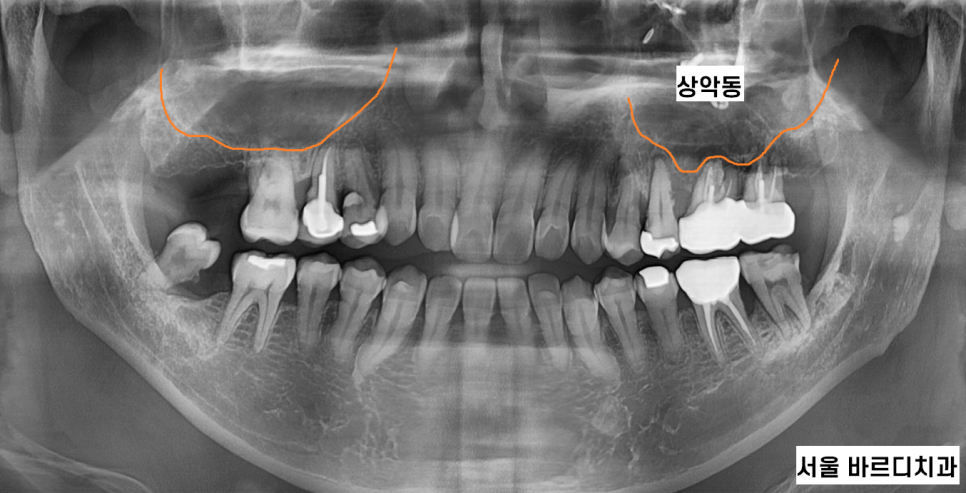

241104 양쪽으로 상악동염이 있어서 뿌옇게 보여요!!!